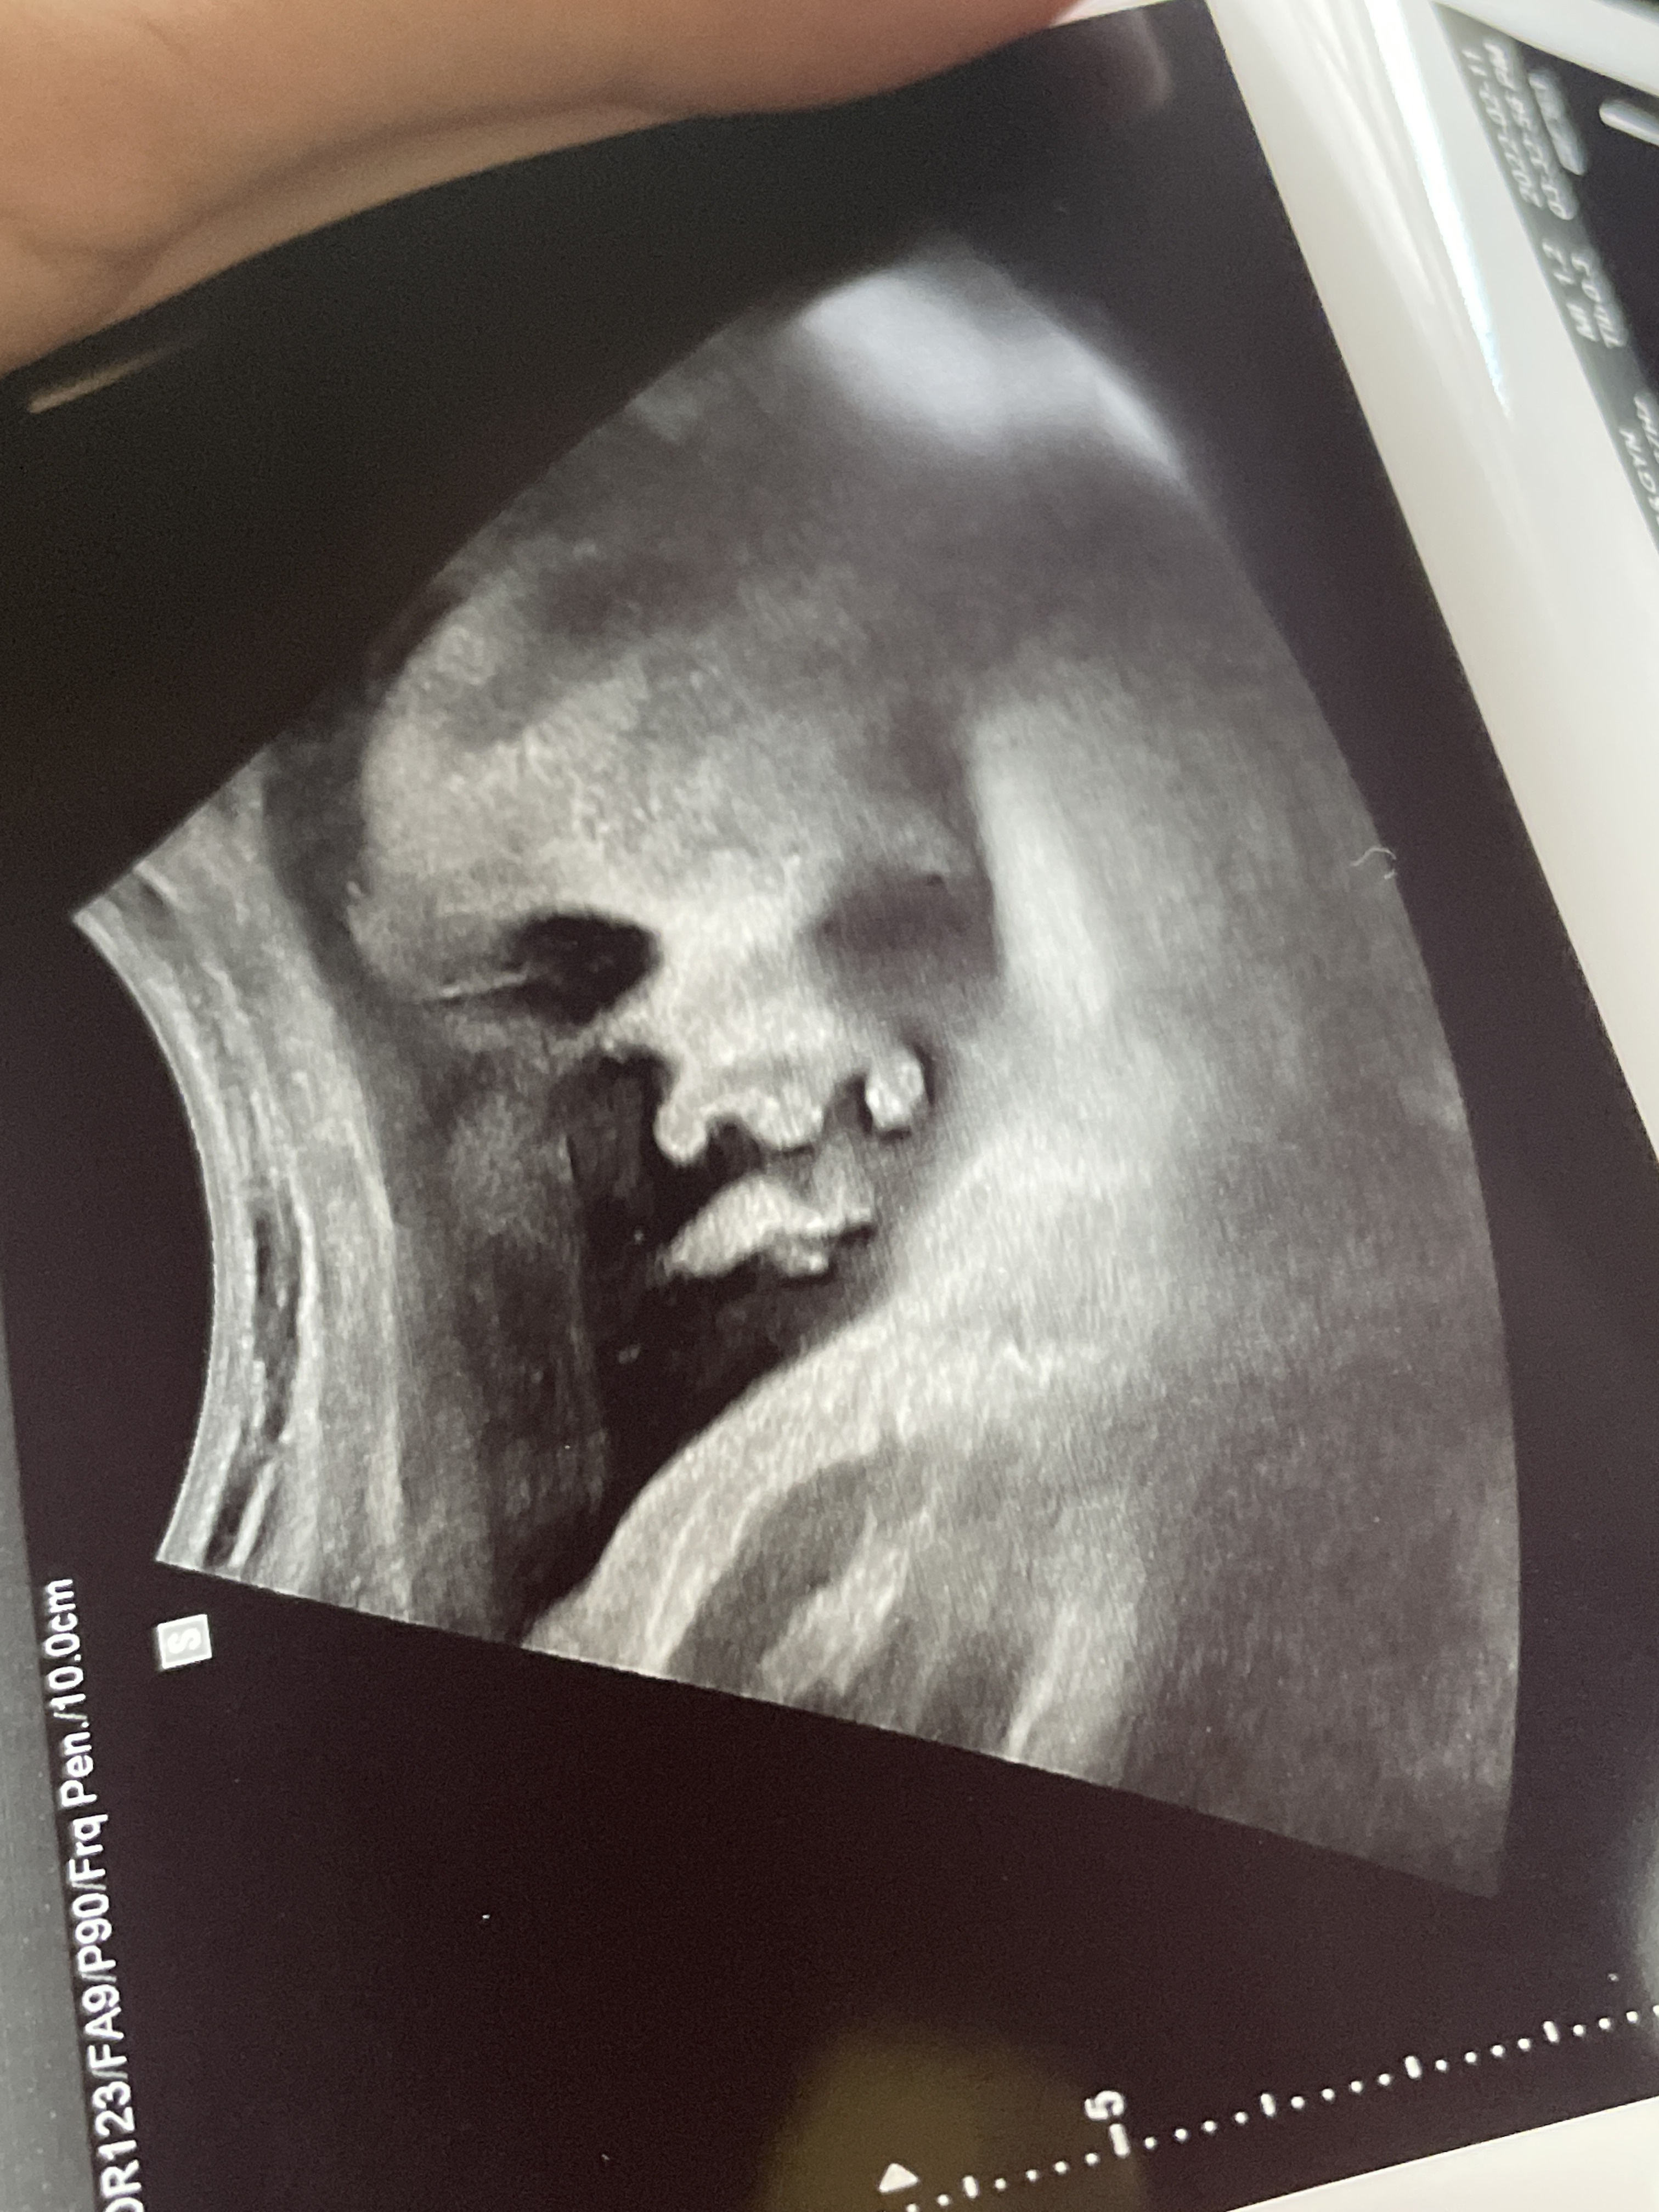

애기가 얼굴이 너무 잘보인다며 웃으셨다.

그와중에 머리는 역시 커졌고,